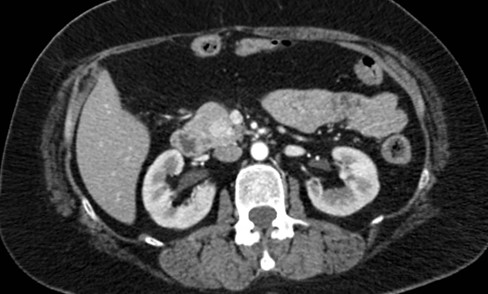

Caso 2

Paciente femenina de 48 años de edad que ingresa a Hospital Sanatorio Franchin por síntomas de cefalea y mareos, cuadro que se hace progresivo, presentando síncopes y posteriormente alteración del estado de conciencia. Los exámenes clínicos revelan una glucosa de 40 mg/dl, concomitante con insulina alta y péptido C elevado. Ingresa de forma programada para realización de duodeno pancreatectomía el 29 de mayo de 2021. Imágenes diagnósticas muestran estudio trifásico de tomografía de abdomen, lesión nodular en la cabeza del páncreas con ávido realce en fase arterial que en resonancia magnética se observa hiperintensa en T2, presenta restricción con la difusión y caída de la señal en el ADC. Además presenta realce tras la administración de contraste con gadolinio.

Estudio histopatológico reveló tumor neuroendocrino bien diferenciado grado 1.

Ahora bien, como se mencionaba al principio, el estudio ecográfico es de muy baja sensibilidad y se identifique o no la lesión por este estudio, nuestro siguiente paso en el algoritmo diagnóstico de esta lesión es la tomografía. Esta es la prueba no invasiva inicial, con una sensibilidad del 63% al 83%, y detecta del 70% al 80% de los tumores. Esta debe realizarse como un estudio trifásico: fase arterial temprana a los 30 segundos, fase venosa a los 70 segundos, fase tardía de 3 a 5 minutos. La característica de estos tumores por tomografía es que se presentan como una masa sólida que tiene un ávido realce en la fase arterial, cuyo realce se mantiene y se observa más tenue en la fase venosa y en los tiempos tardíos la lesión se homogeniza.

Para mi caso, y dando una visión general de los métodos de imagen no invasivos en esta revisión retrospectiva, solo a uno de los pacientes se le detectó la lesión por ecografía, donde se visualizó una lesión nodular hipoecogénica en el cuerpo del páncreas. A los demás pacientes se les detectó la lesión por tomografía en estudio trifásico, donde resaltan las características ya descritas por la literatura de lesiones hipervasculares con intenso realce en fase arterial, localizadas en diferentes partes del páncreas, como cabeza, cuerpo y cola.